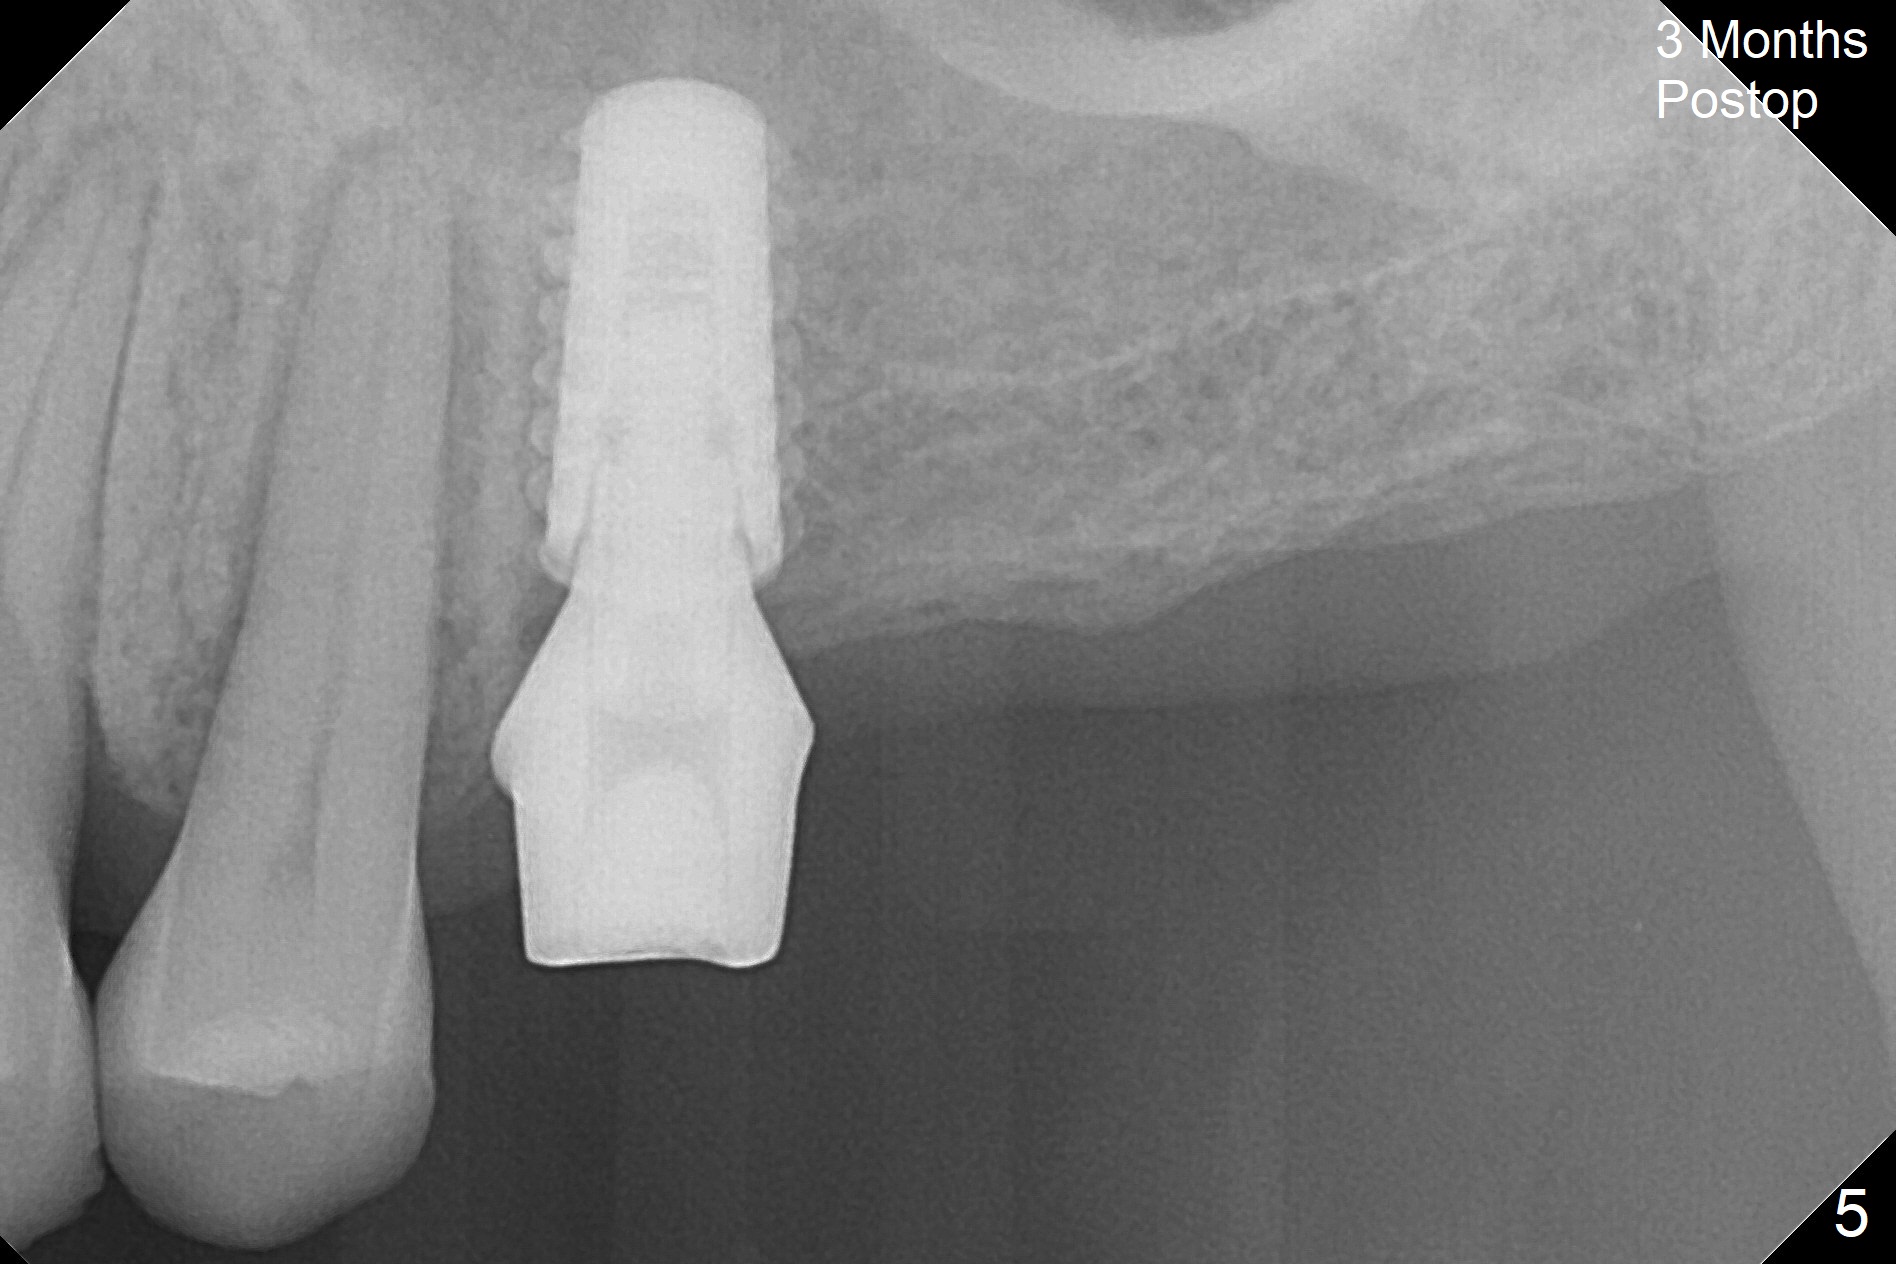

The long 4.8 mm Magic Drill (MD) is used as a tissue punch at the site of #14. After use of a curette to remove the tissue, the MD is used for osteotomy. In fact the osteotomy is mesial with an increase in the osteotomy depth. Magic Lifter, Magic Expander (3 mm) and Magic Drill (3.8 mm) are used to finish sinus lift. Following placement of PRF and Vanilla Graft, a 4.5x11 mm dummy implant is placed (Fig.1,2). The osteotomy seems to be mesial. After use of Lindamann bur distally and 2nd round of PRF membrane and Graft, a 5x9 mm implant is placed > 50 Ncm (Fig.3,4). The final implant appears to remain mesially radiographically. Retrospectively, 1.6 mm pilot drill should have been used with insertion of guide pin after tissue punch. Change in osteotomy position would have been much easier at the early stage. The patient returns for impression 3 months postop; There appears to be space mesial to the implant (Fig.5). The permanent crown will be cemented 2-3 months later. No screw loosens probably related to mesial placement of the implant.